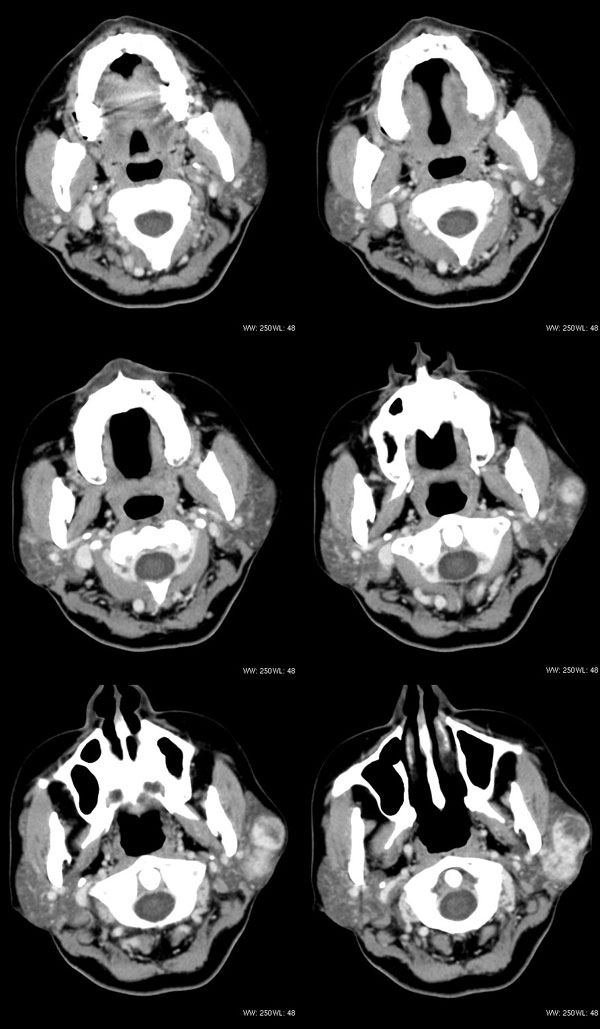

女性,43岁。左腮部肿物5年。体检:(肿物)质中,约5x4x4cm,边界清,固定。

左腮腺肿物,内可见低密度坏死区,增强扫描示肿块明显强化,且呈持续延迟强化,常规考虑腮混合瘤可能性大,但强化表现不太符合,不除外腮腺纤维血管瘤、神经鞘瘤、淋巴瘤及巨淋巴结增生症

考虑左侧腮腺混合瘤。  肿瘤较大,边清,囊变,强化明显,皮肤及淋巴结无异示

左侧腮腺多形性腺瘤可能性大。1、是混合瘤中最常见的良性肿瘤;2、中年女性多见并且时间长症状轻;3、病灶内有低密度坏死区,增强时强化;4、其内有钙化,囊性部分未强化;5、需与囊性淋巴瘤相鉴别。